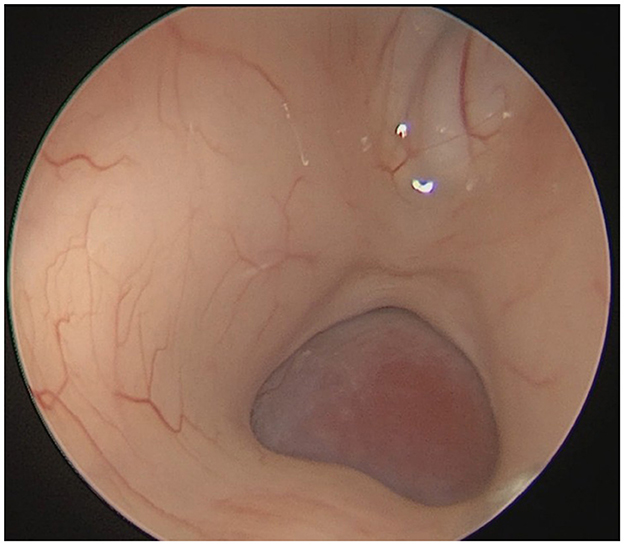

A 22-year-old male presented with intermittent dizziness and headache lasting for 2 weeks. MRI at admission revealed a cystic mass in the pineal region, accompanied by supratentorial hydrocephalus (Figures 3–5). No surgical contraindications were identified. After discussion with the patient's family, neuroendoscopic resection was performed via the Transfrontal-Transventricular-Transforaminal Approach. Intraoperatively, a 20 × 20 mm soft, well-vascularized tumor was found obstructing the cerebral aqueduct. The lesion had well-defined margins and was carefully dissected from surrounding adhesions, preserving adjacent veins and brain tissue. Macroscopic total resection was achieved en bloc (Figures 6–8). Postoperative day 1 MRI confirmed complete tumor removal and resolution of hydrocephalus (Figures 9–11). Postoperatively, no complications were observed. However, due to personal reasons, the patient was discharged on postoperative day 11. Histopathology confirmed a mixed germinoma. No recurrence or surgery-related complications were noted during follow-up.

Figure 6

Intraoperative endoscopic view showing a ~20 × 20 mm tumor obstructing the cerebral aqueduct in the pineal region.